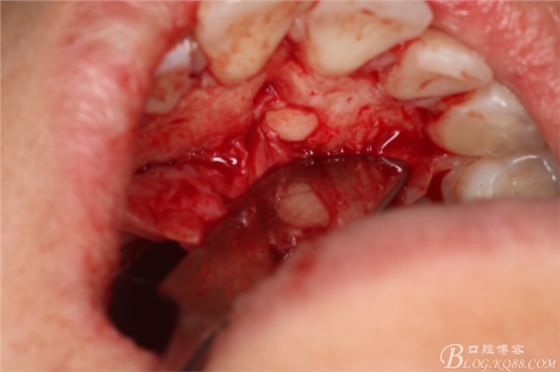

圖8.翻瓣暴露出鼻腭神經(jīng)管及腭側(cè)骨面

圖9.在切牙管旁邊去骨、暴露出21根尖區(qū)多生牙牙根